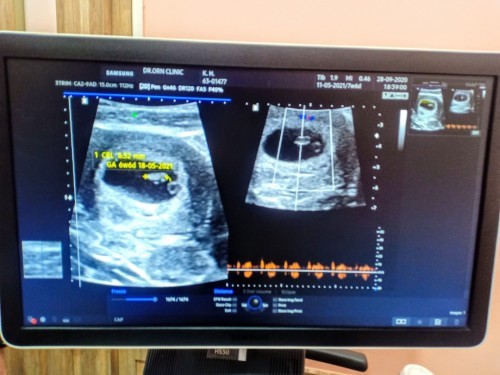

7 วีค ทางหน้าท้อง เจอถุงตั้ครรภ์ เจอหัวใจเต้น เจอถุงไข่แกงแล้วค่ะแม่